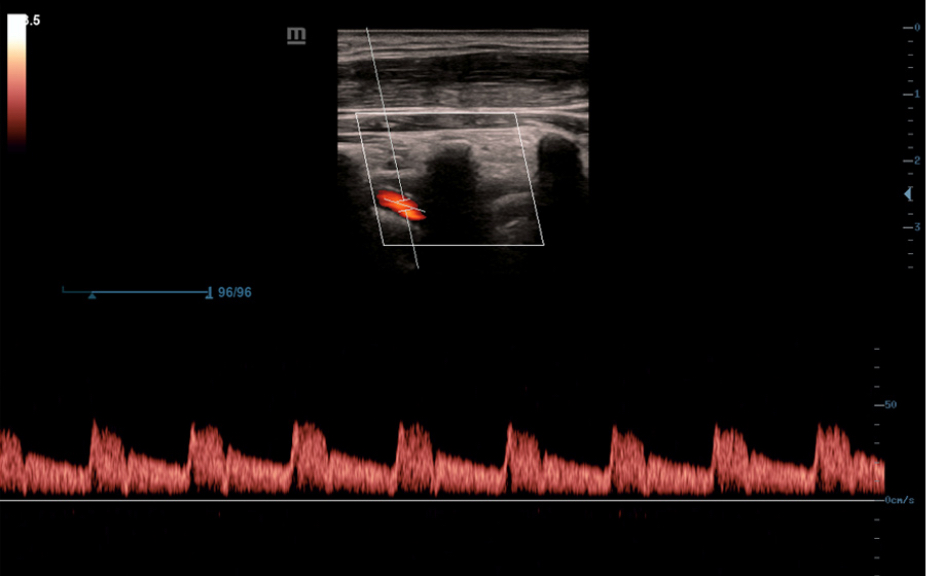

Анатомические иллюстрации, включающие схемы и УЗИ-изображения.

Боковое отображение стандартной эхограммы, обеспечивающее визуальное наведение на изучаемую область.

Стандартные эхоизображения

3

Сравнение результатов сканирования в реальном времени для справки.